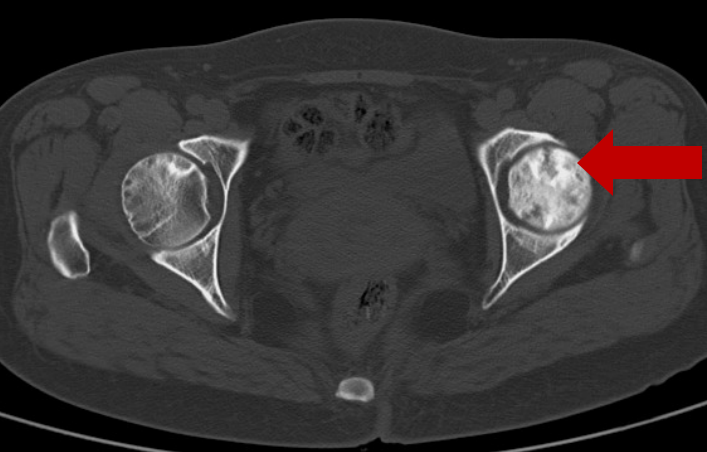

2020年8月6日CT:左股骨头囊样坏死区

在2020年8月7日的时候,进行了一次介入手术,以及相关中医药综合治疗,在2020年10月12日,又进行了第二次介入手术,还有相关中医药综合治疗,之后,左下肢酸痛不适的情况消失了,患者恢复了正常生活。